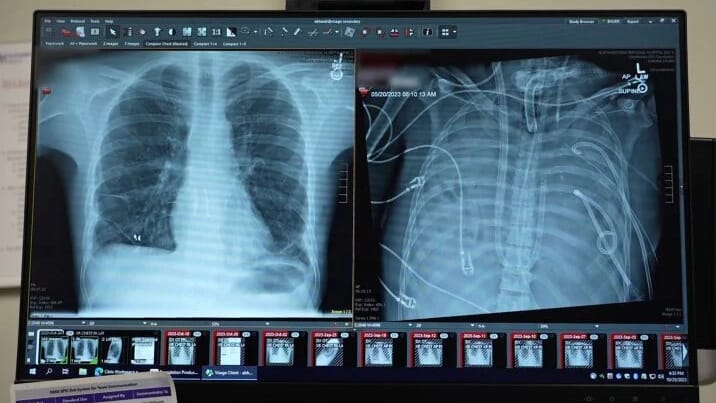

A 33-year-old man became critically ill after a severe infection destroyed his lungs. What began as the flu quickly turned into acute respiratory distress syndrome (ARDS) and bacterial pneumonia. His lungs filled with fluid. They stopped working. His heart and kidneys began to fail, too.

Doctors had no other option. They removed both lungs to stop the infection from spreading further.

Normally, that means death. But instead, doctors connected him to an advanced artificial lung system. For 48 hours, the machine kept him alive. Donor lungs became available in time. Surgeons performed a successful double lung transplant. The patient recovered fully and returned to normal life.